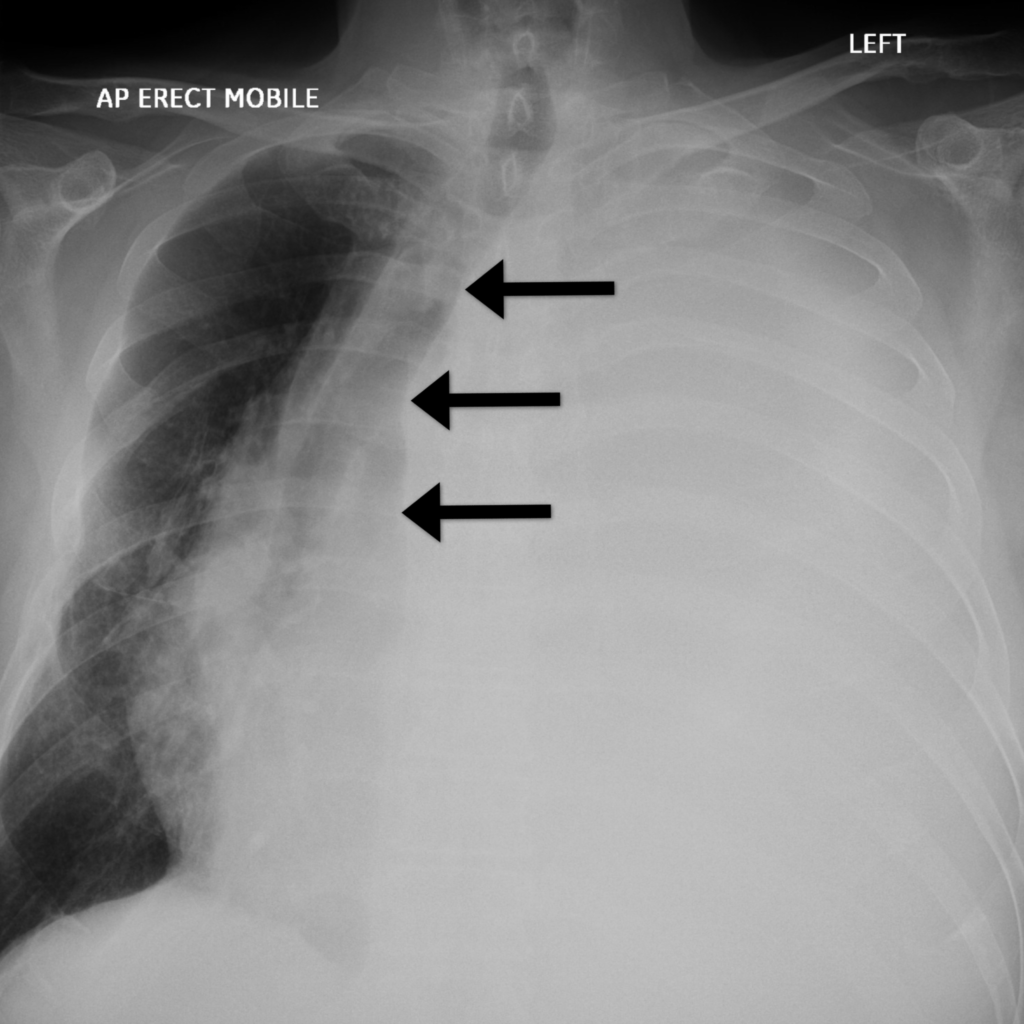

The X-ray is clearly not normal. The left side is completely opacified: this can be termed a white-out. By looking at the mediastinum we can try and work out the cause.

In this case we can see the mediastinum is pushed away from the white-out: look at the position of the trachea in the X-ray below.

Given there is movement away from the white-out we have to strongly suspect a pleural effusion. The fluid within the pleural space occupies volume which exerts pressure upon the mediastinum.

In this case the trachea is deviated to the right, pushed away from the white-out suggesting a pleural effusion